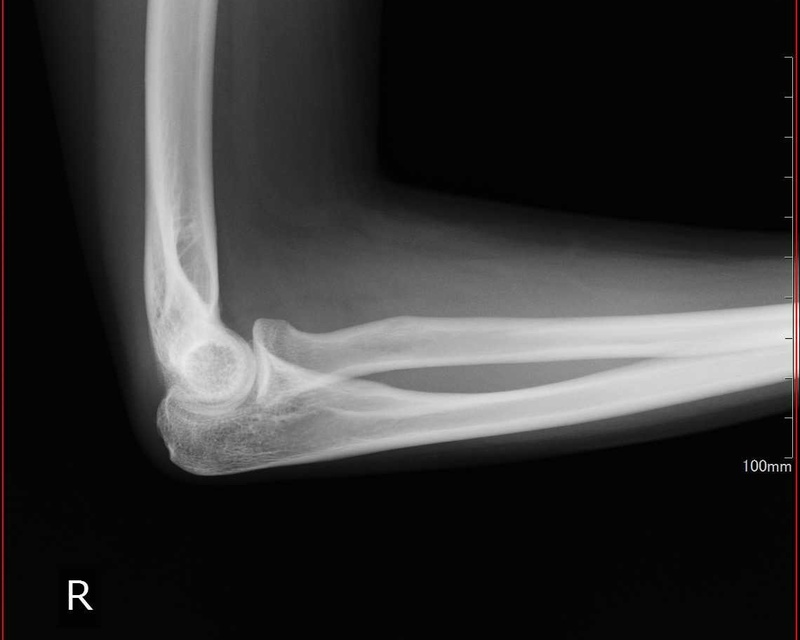

レントゲン検査

テニス肘は腱の炎症のため、レントゲン検査を行っても通常、骨には異常が見られることはありません。

しかし、変形など他の疾患との鑑別や稀な腫瘍などを区別するためにも必須です。

また、テニス肘も症状が進行して慢性化しているケースでは、腱にカルシウムを主とした沈着物が溜まることがあり、レントゲン検査時で判別することが可能です。